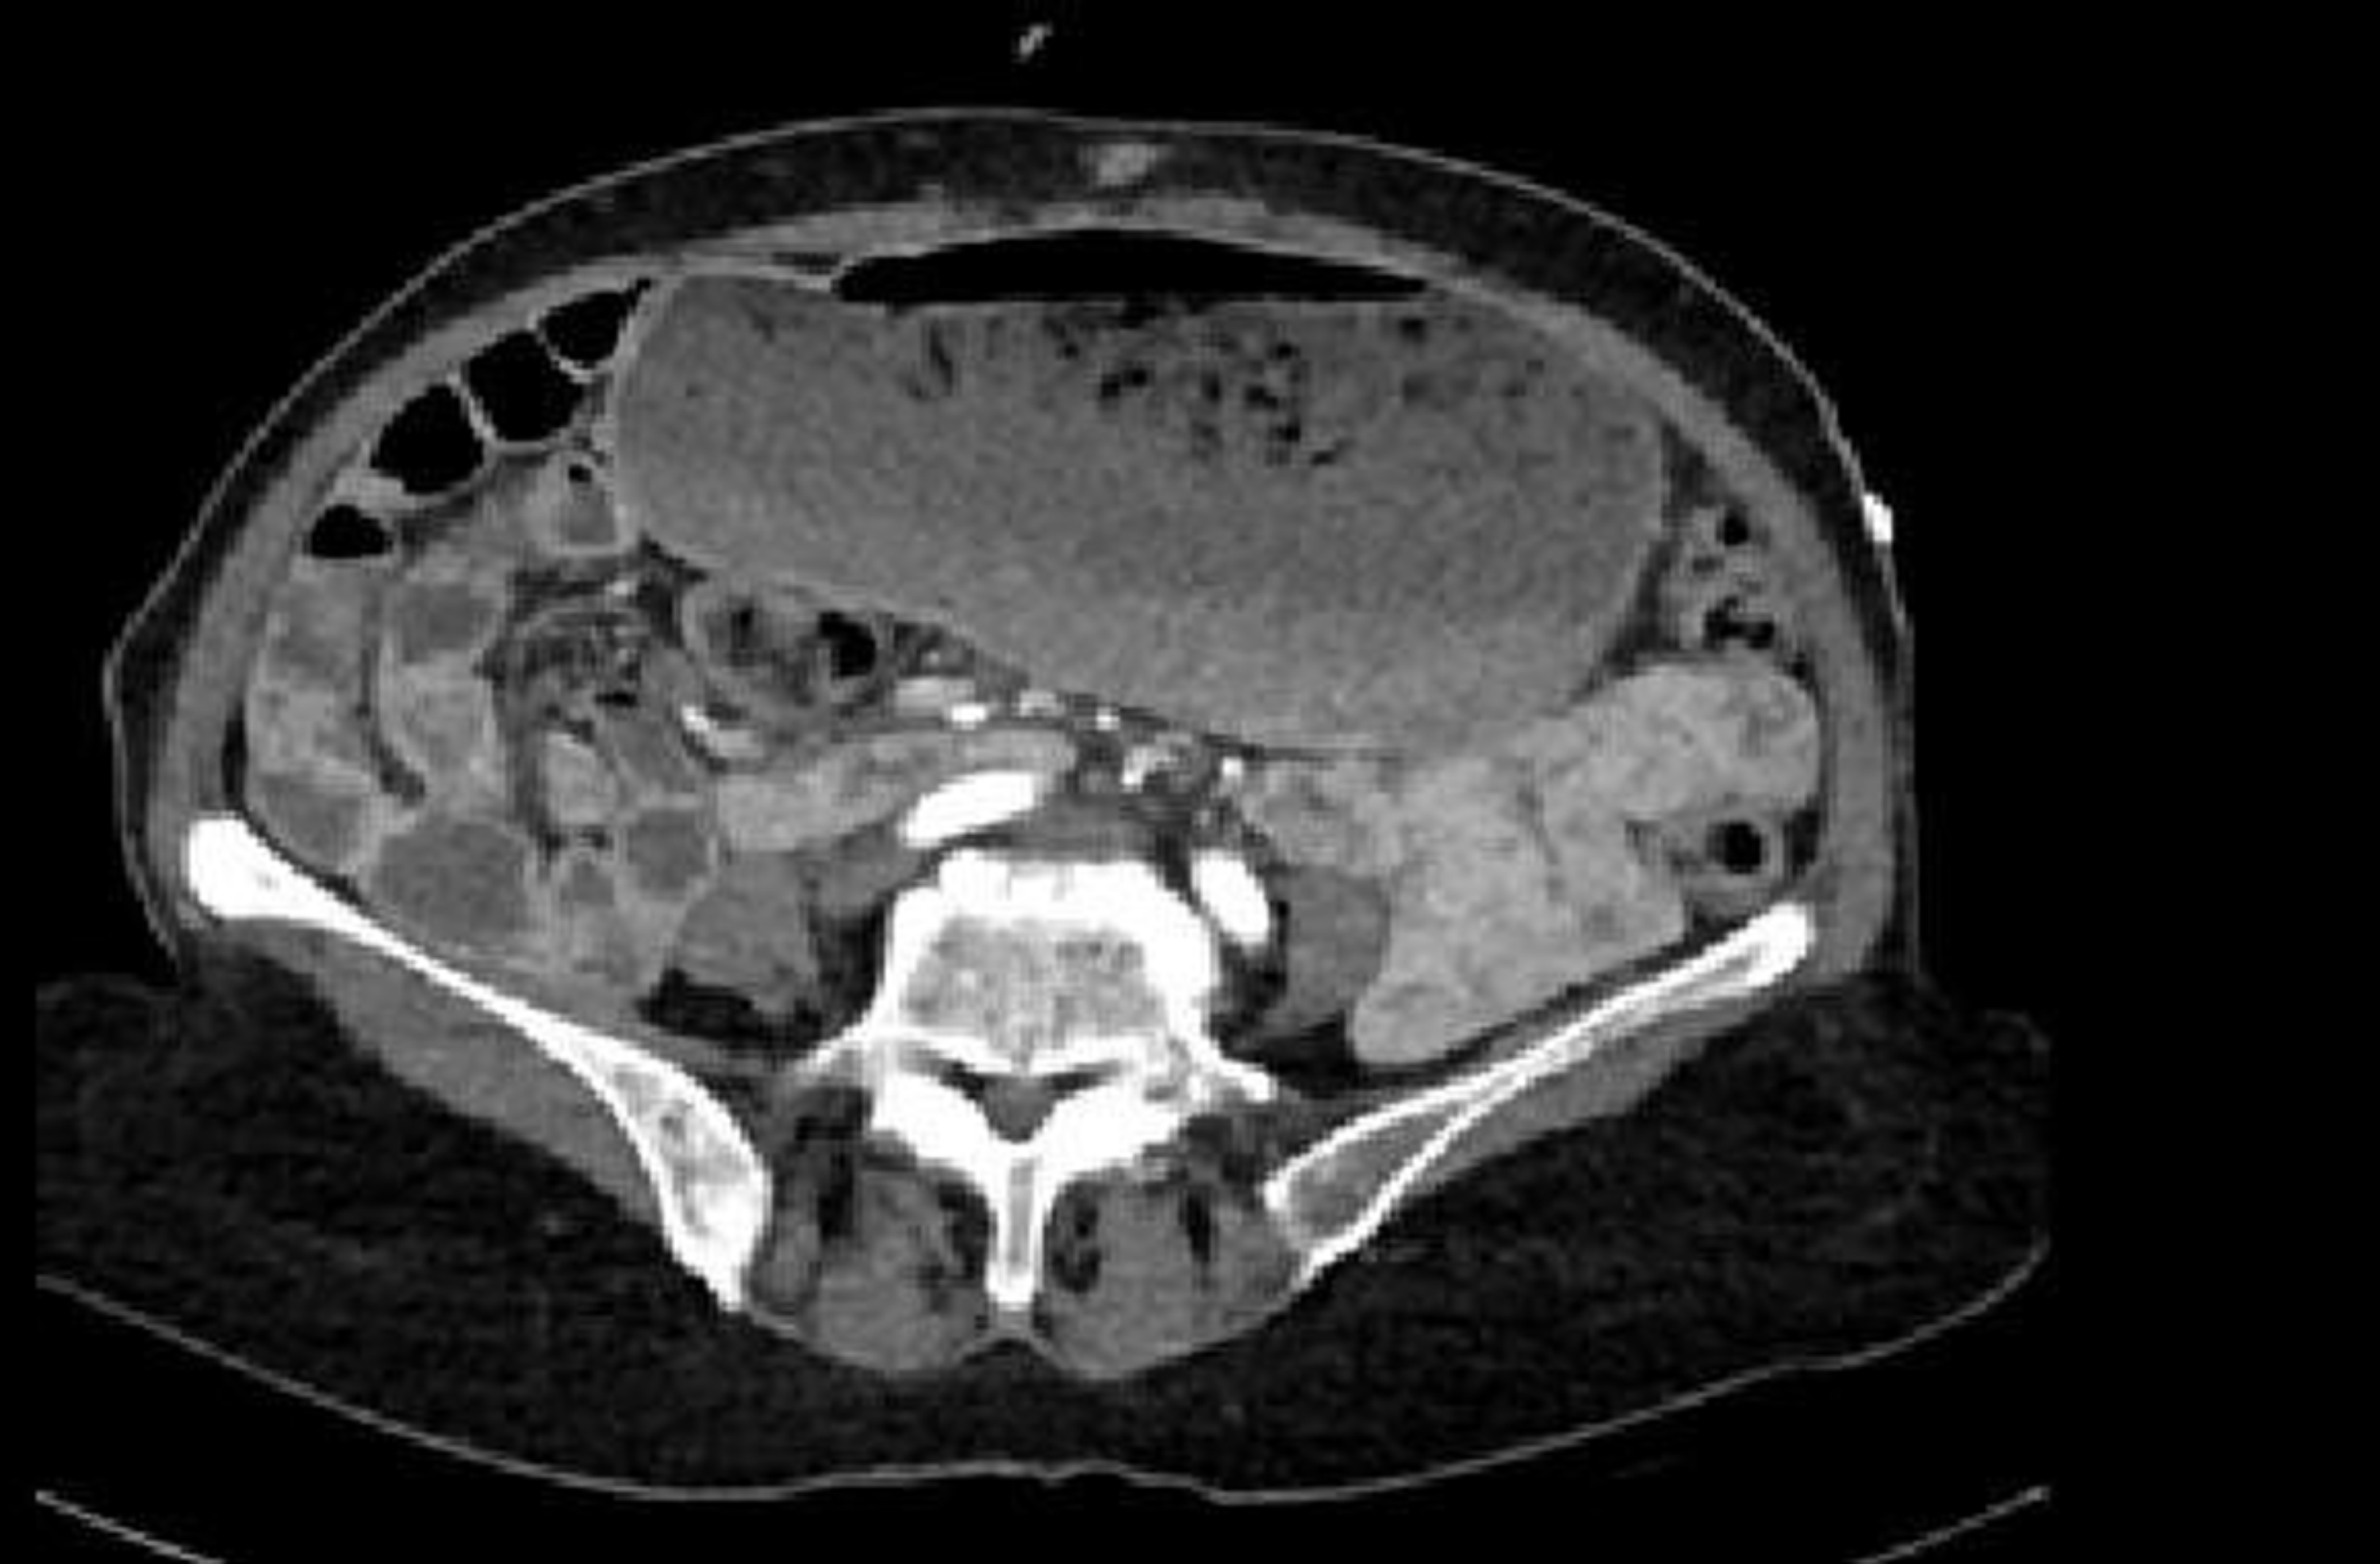

Abdominal CT angiography revealed no thrombus or ischemic findings in the vessels or intestines, but the stomach was distended with dense content (Figure 1, Figure 2). The stomach appeared to be in a hypotonic state, and its size extended to the pelvis. Diabetic gastroparesis was suspected, and the patient was admitted to the general surgery ward for treatment and follow-up.

In one case, a barium study showed a decreased gastric emptying rate and gastric dilation.4 In another, a barium radiologic examination revealed the absence of esophageal peristalsis, gastric dilation, and solid food remnants.5 In a case reported by Tonzi et al., after no improvement with frequent and small meals, an endoscopy was performed, revealing an incompetent lower esophageal sphincter and undigested food particles in the stomach, leading to the diagnosis of diabetic gastroparesis. In our case, abdominal CT angiography showed a distended abdomen with dense content, and no further tests were performed since gastroparesis was suspected based on the CT findings. Dynamic contrast imaging was used to observe the progression of contrast through the gastrointestinal system.

Figure 1. Transverse plane of the stomach on abdominal CT